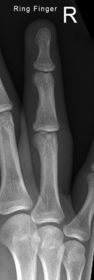

| What's the evaluation criteria for the PA Finger X-Ray? | ANATOMY: distal phalynx -> distal 1/2 of metacarpal demonstrated CRITERIA: - equal concavity on both sides of phalanges - IP and MCP open - no overlapping of adjacent fingers POSITIONING: CR perpendicular @ PIP joint |

| What's the evaluation criteria for the Lateral finger x-ray? | ANATOMY: entire digit demonstrated CRITERIA: open joint spaces concave to one side, while the dorsal side is straight no overlapping of adjacent fingers/soft tissues POSITIONING: CR perpendicular @ PIP joint |

| Oblique finger x-ray image criteria? | ANATOMY: entire digit demonstrated CRITERIA: more concavity to one side open joint spaces no superimposition of adjacent fingers POSITIONING: CR perpendicular @ PIP joint |